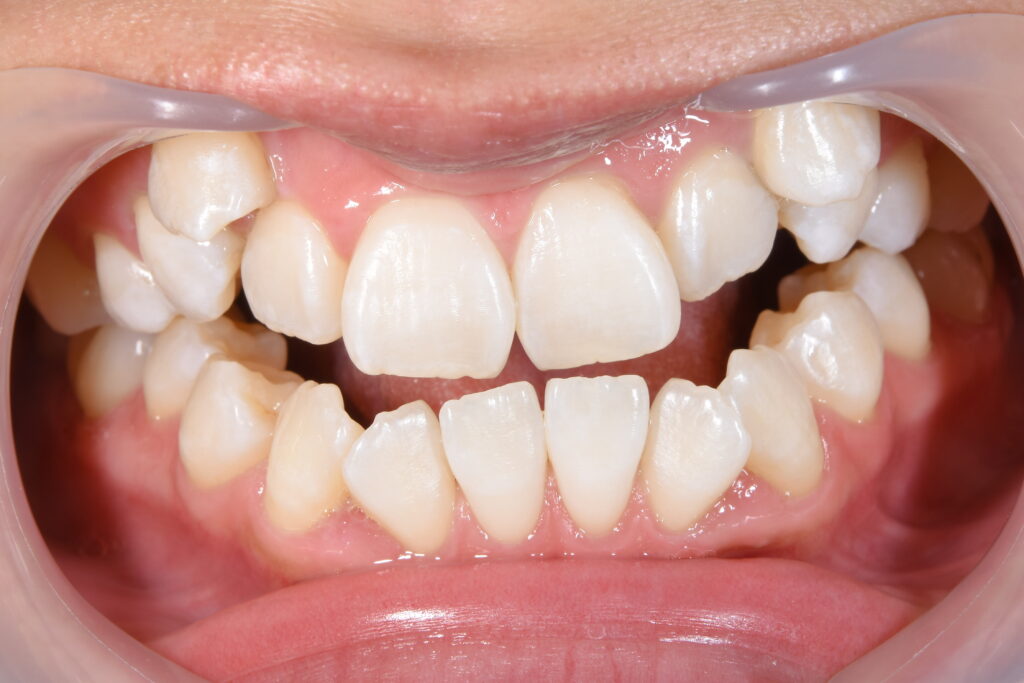

まずは初診時です。

【初診時】

今回ご紹介の患者様の問題点

①叢生(歯のがたつき)→清掃性が悪く将来虫歯・歯周病リスクが高くなる

②開口(奥歯しか噛んでいない)→かみ合わせが原因で、将来的に奥歯が痛くなる

③審美的問題

以上の問題点より、矯正治療を開始致しました。

今回の治療計画は上下小臼歯の抜歯を行いました。

治療装置はインビザライン(マウスピース)です。針金は使用しておりません。